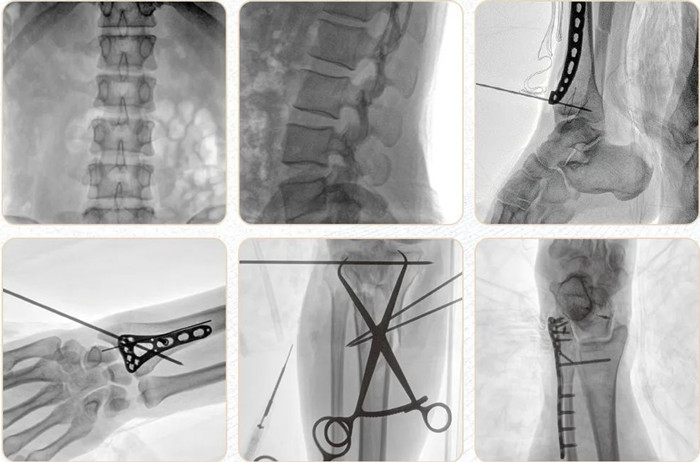

移動式平板C形臂PLX118F-Plus臨床應用范圍:可應用在骨科、普通外科、矯形外科、創(chuàng)傷外科、泌尿外科、脊柱外科、疼痛外科、消化科、腫瘤科、婦產(chǎn)科等科室。